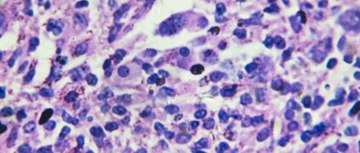

ICIs are standard of care for many tumor types commonly seen in SOT. ICIs are monoclonal antibodies designed to block inhibitory pathways of the immune system, thereby enhancing activation and proliferation of T cells. With advancements in our understanding of the immune system, the mechanisms by which ICIs bolster immune activity have also evolved. Current ICI options include inhibitors of programmed cell death protein 1 (PD-1), programmed cell death-ligand 1 (PD-L1), lymphocyte-activation gene 3 (LAG-3) and cytotoxic T-cell lymphocyte associated protein 4 (CTLA-4). One major concern for using ICIs in transplant recipients is the increased risk for graft rejection.2,7 While graft rejection is multifactorial, a major component is T-cell stimulation and activation which leads to cytotoxic effects on the donor organ.7 PD-L1 and PD-1 receptors can be expressed by the tumor, the graft, and graft-reactive T cells. Expression on the graft and graft-reactive T cells is associated with a greater risk of acute rejection.2,8 Furthermore, PD-L1 is expressed on endothelial cells of the graft which has been attributed to developing vascular rejection in the setting of anti-PD-1/PD-L1 therapy.9 Graft rejection can occur rapidly, with studies reporting an observed median time to rejection of approximately 3 weeks, and most episodes of rejection occurring within 7 weeks.2,10,11